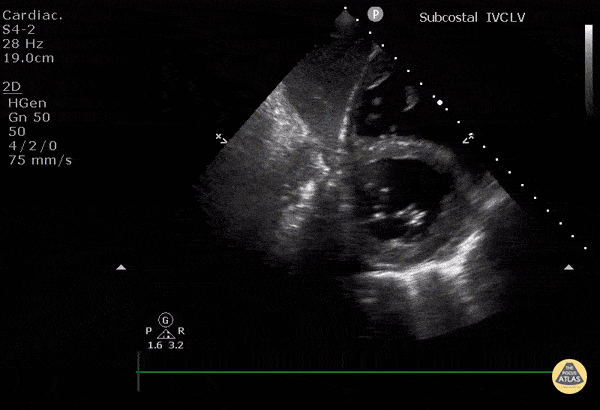

Normal Cardiac Anatomy - Subcostal Short Axis

WCUME17 Submission for "Novel Indication" Subcostal short axis view of the left ventricle can be useful if PSAX window is poor. A good alternative to estimate LV function. This image shows: LV in short axis at level of MV and the RV in short axis, and the interventricular septum. The liver is overlying. Technique: Start with IVC in long axis at entrance to RA and tilt transducer cephalad. Slide transducer to patient's right, fan transducer out to patient’s left. Dr. Cian McDermott - Dublin, Ireland